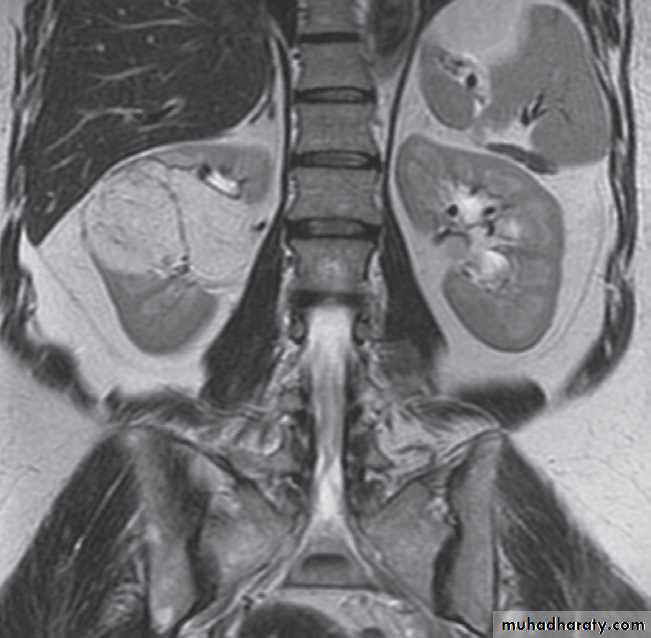

-Congenital intrinsic pelviureteric junction obstruction(PUJ obstruction ):The diagnosis depends on identifying dilatation of the renal pelvis and calices, with an abrupt change in calibre at the PUJ with normal ureter .

Ultrasound Dilatation of the pelvicaliceal system ( hydronephrosis ) is demonstrated sonographically as a multiloculate fluid collection in the central echo complex, caused by pooling of urine within the distended pelvis and calices .

Major DDX are multiple renal cysts. With prolonged obstruction, thinning of the cortex due to atrophy will be seen.